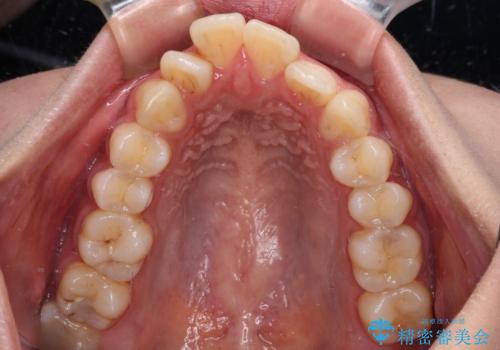

- 前歯の突出感とデコボコを気にして来院された患者様です。

奥歯の噛み合わせをみると、上顎歯列が全体的に前突している状態であり、この咬み合わせのまま歯列を整えると出っ歯になってしまう可能性がありました。

アンカースクリューと補助装置を使用して上顎大臼歯を遠心移動させることで咬み合わせを改善し、更には口元の突出感を改善するために上下左右の小臼歯4本を抜歯し、ワイヤー装置によりデコボコを解消しながら口元の突出感も改善していくこととしました。